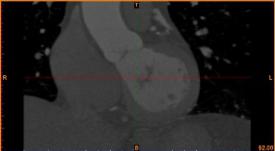

首先通過病人的心臟冠脈造影CT數據,獲取病人的心臟冠脈三維模型。

病人的冠脈造影CT數據                                                                       提取出的冠脈三維數據